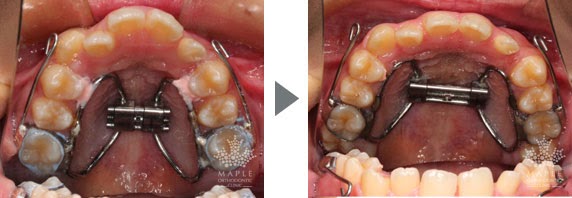

急速拡大装置と上顎前方牽引装置を用いた12か月の変化です。

前歯の反対咬合(受け口)が改善しました。

上顎の横幅も広がりました。